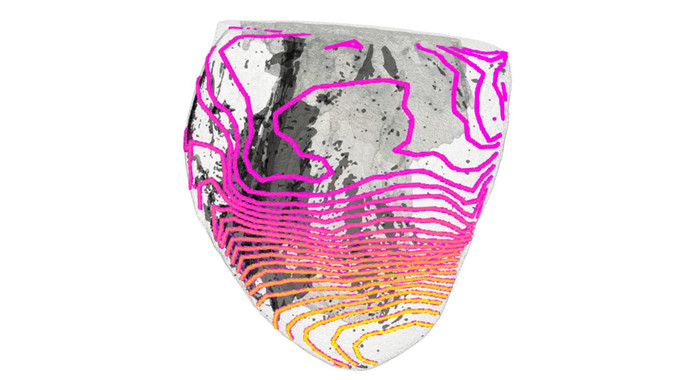

| ▲ 심장 근육의 흉터 조직은 전기 자극(색깔 있음)의 전달을 방해하지만, 항상 그런 것은 아니다. 따라서 심장 부정맥과 급성 심장사는 종종 운동 중에만 발생한다. © 프라이부르크 대학 병원 |

영상은 심장의 흉터 조직이 항상 심장 기능을 방해하는 것은 아니라는 것을 보여주었다. 오히려 심박수에 따라 심장의 전기 신호 전달을 변화시킨다. 정상적이고 차분한 심박수에서는 전기 자극이 변형된 조직을 거의 방해받지 않고 통과한다. 따라서 이러한 흉터의 영향은 정상적인 조건에서는 일반적으로 감지되지 않는다.

"저역 통과 필터"로서의 흉터 조직그러나 신체 활동이나 심한 스트레스 시에는 이러한 현상이 변한다. 심장이 더 빨리 박동하면 심장 근육의 전기 신호가 흉터 조직에 의해 약화되거나 차단된다. "이는 스트레스가 적을 때 정상으로 보이는 심장 부위에서도 심장 부정맥이 재발하는 것을 촉진한다"고 연구진은 설명했다. 최악의 경우, 전도 장애가 너무 심해 심장이 완전히 멈춘다.

지아르디니와 그의 동료들은 이러한 주파수 의존적 효과를 기술적 "저역 통과 필터"에 비유했다. 빠른 펄스는 특정적으로 감쇠되는 반면, 느린 펄스는 영향을 받지 않는다. 지아르디니의 동료인 피터 콜은 "우리 연구는 심장의 흉터 조직이 단순히 방해하는 것이 아니라 심장 기능에 적극적으로 영향을 미친다는 것을 보여준다"고 말했다.